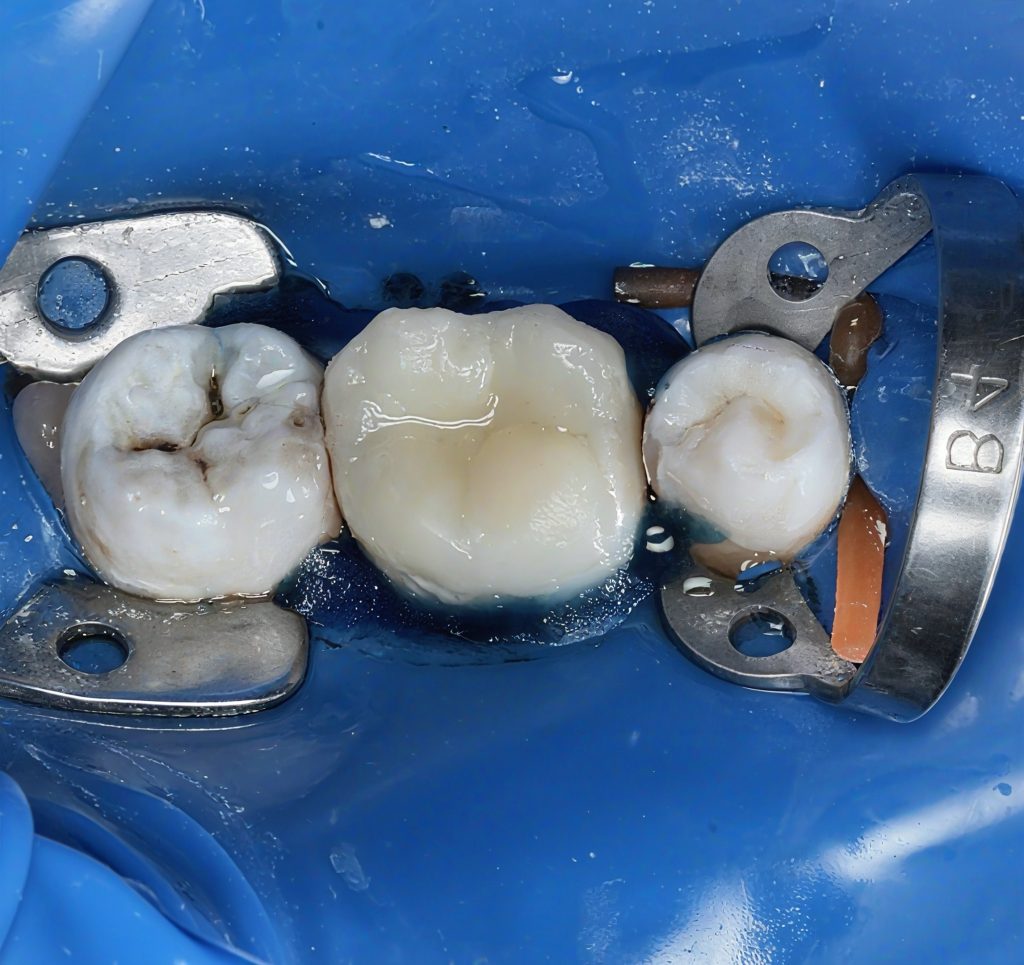

1. Pre-operative Status

(Image 1)

Large MOD cavitation with deep discoloration and compromised cuspal support. Tooth remained restorable with a conservative adhesive and endodontic approach.